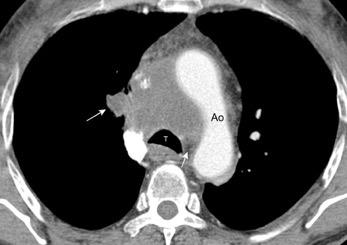

85. ENSANCHAMIENTO MEDIASTÍNICO AGUDO

102. HEMATOMA MEDIASTÍNICO.

Hematoma intramural

Disección aórtica

Rotura de aneurisma aórtico

Hematoma mediastínico post-cirugía aórtica con alta densidad y derrames pleurales (densidad baja)